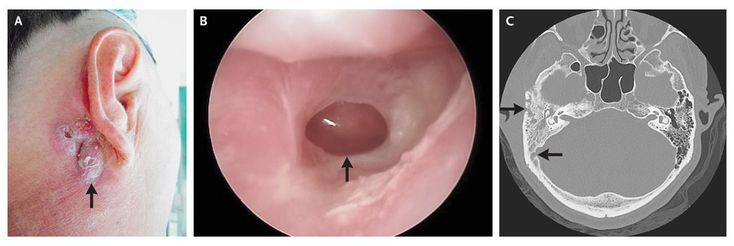

Acute mastoiditis in a child. The pinna has been pushed forward ...

Acute mastoiditis with facial paralysis as initial symptom of ...